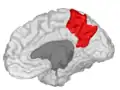

![]() Medial surface of left cerebral hemisphere. (Precuneus visible at top left.) (Anterior to the right.) | |

![]() Sagittal MRI slice with the precuneus shown in red. (Anterior to the left.) | |